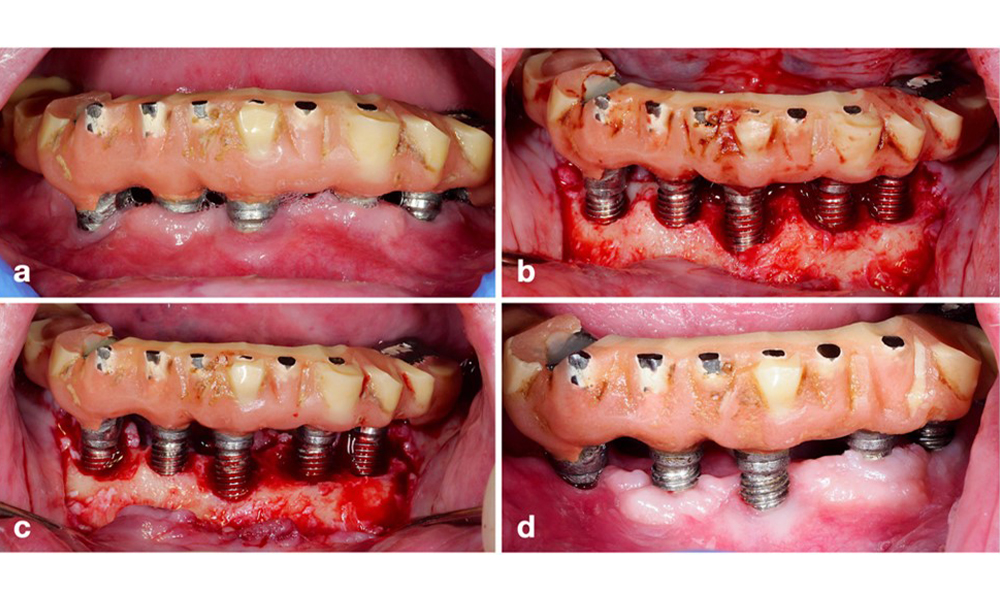

По време на Световния семинар за класификация на пародонталните и периимплантни заболявания и състояния през 2017 г. бяха определени диагностичните критерии за периимплантатен мукозит и периимплантит (Renvert et al. 2018). Периимплантният мукозит се дефинира като (1) наличие на възпаление около импланта (т.е. зачервяване, подуване, линия или капки кръв в рамките на 30 секунди от сондирането), но (2) без допълнителна костна загуба след първоначалното заздравяване (фигура 1 ).

Имплант в позиция 26 с периимплантатен мукозит (a–c). Дълбочината на сондиране от 5 mm (b) съответства на измерването, направено няколко седмици след поставянето на протезната реконструкция. Има кървене при сондиране (c), но рентгеновата снимка не показва допълнителна костна загуба извън очакваната при маргинално костно ремоделиране (d).

Фигура 1. Имплант в позиция 26 с периимплантатен мукозит (a–c). Дълбочината на сондиране от 5 mm (b) съответства на измерването, направено няколко седмици след поставянето на протезната реконструкция. Има кървене при сондиране (c), но рентгеновата снимка не показва допълнителна костна загуба извън очакваната при маргинално костно ремоделиране (d).